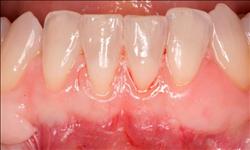

Normally gum tissue surrounds and protects the delicate roots of your teeth. Exposed tooth roots are prone to tooth decay, root canals, discoloration and actual jawbone loss. All of this can lead to tooth loss in advanced cases.

Functional Soft Tissue Grafting replaces the missing gum tissue and protects your teeth. For this reason, soft tissue grafting may be recommended even for back teeth.